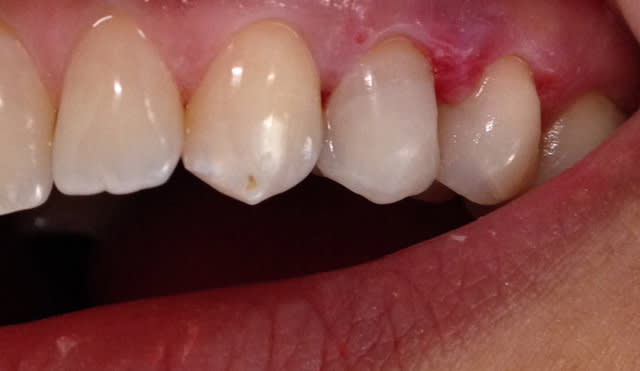

Alors comment traiteriez vous cette 24 asymptotique, qui présente un enorme délabrement sous gingival , notez que l'émail n'est plus soutenu par la dentine à aucun endroit ?

1ère séance remontées de la marche distale au compo flow + compo de restauration / réalisation d'un IDS , le tout sous digue bien sur (voir radio jointe , désolé à l'envers))

Voici les photos toutes fraiches de ce matin.

Vos critiques sont bien sur les bienvenues je dois encore beaucoup m'améliorer sur les prises de teintes, et je m'y attelle en ce moment,, par contre en ce qui concerne la pérennité de la restauration…..ma patiente a sa dent bien vivante, aucun joint sous gingival , possibilité de réaliser une endo dans le futur sans détruire la restauration existante si besoin, possibilité re refaire un onlay dans quelques années si ça casse, toujours sur dent vivante…. bref la liste des avantages est très longue par rapport au classique endo-IC-CCM.